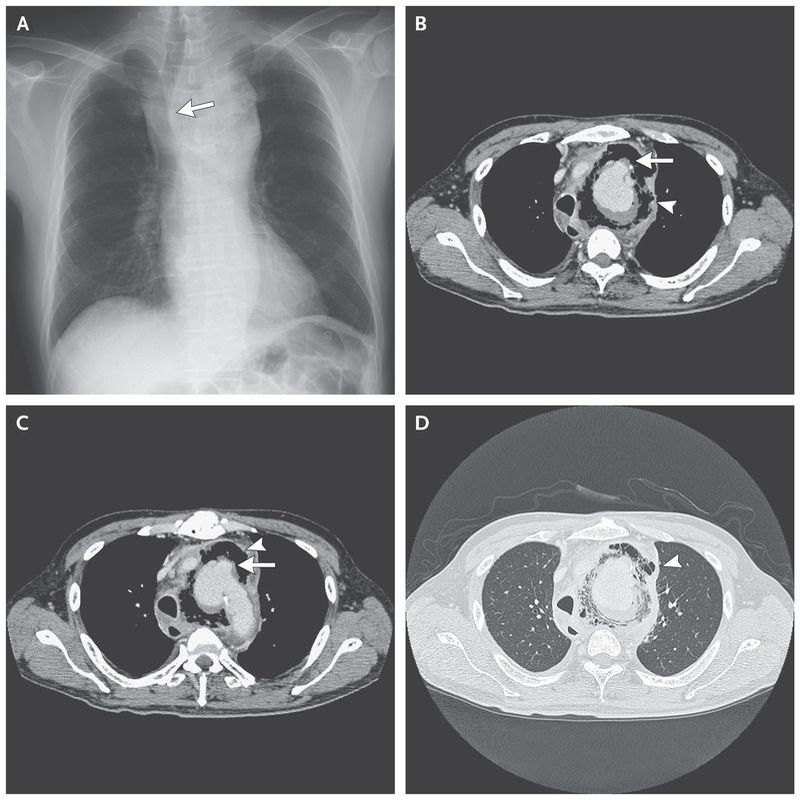

A 66-year-old man with hypertension presented with a 1-month history of fever and 4 days of hoarseness. He reported no chest pain, cough, or dyspnea. His temperature was 38.7°C, but the remainder of the physical examination was unremarkable. The peripheral-blood leukocyte count was elevated, and a chest radiograph showed enlargement of the aortic arch, with deviation of the trachea to the right side (Panel A, arrow). Computed tomography of the chest revealed a pseudoaneurysm in the aortic arch (Panels B and C, arrows), surrounded by extensive gas collection (Panels B, C, and D, arrowheads). Treatment with piperacillin–tazobactam was started. Blood cultures grew Salmonella enterica,and a diagnosis of salmonella aortitis was made. The patient had a sudden collapse on rupture of the infected aneurysm and underwent urgent graft-replacement surgery followed by stent replacement after the postoperative development of an esophageal fistula. The patient initially recovered but died from an unknown cause several months after surgery. The infection of an aneurysm of the aortic arch with salmonella species is rare and is associated with high morbidity and mortality.